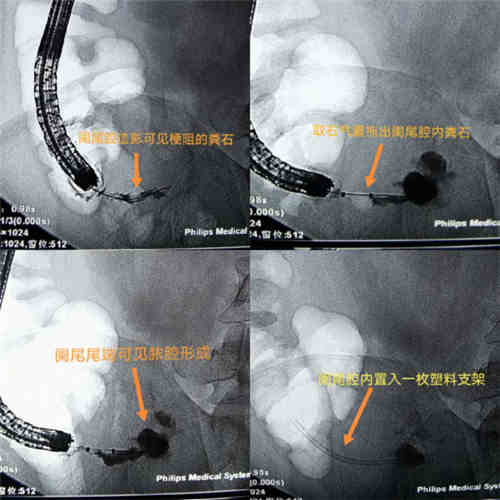

患者男性,因右下腹部疼痛不适入院,诊断为急性阑尾炎,CT提示阑尾周围脓肿形成并局限性腹膜炎。经保守治疗后病情无明显好转,医院普外科与消化内镜中心副主任曹鹏在反复分析病情后与病人沟通,制定了ERAT治疗方案。由于内镜下阑尾插管是整个ERAT技术的核心,加上阑尾较短,且在腹腔外游离度相对较大,所以插管较为困难。正常的阑尾开口是被Gealach’s瓣覆盖,会造成插管困难。于是在锥形透明帽的帮助下推开Gealach’s瓣,并进行阑尾逆行插管。随后,在内镜在X线引导下用取石气囊取出粪石,抽出大量脓液,并用甲硝唑进行阑尾冲洗引流,再成功为患者放置了内置引流管,手术用时1小时,患者术后腹痛等症状明显缓解,对内镜治疗效果非常满意。